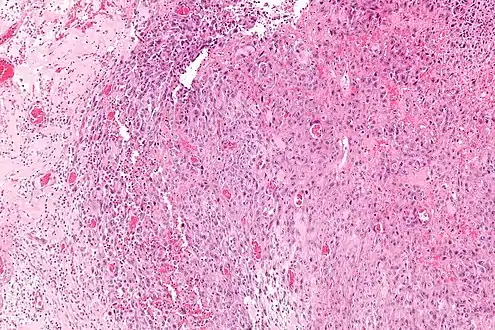

Histologically, epithelioid sarcoma forms nodules with central necrosis surrounded by bland, polygonal cells with eosinophilic cytoplasm and peripheral spindling.[3] Epithelioid sarcomas typically express vimentin, cytokeratins, epithelial membrane antigen, and CD34, whereas they are usually negative for S100, desmin, and FLI1 (FLI-1).[3] They typically stain positive for CA125.[4]

Intermed. mag.